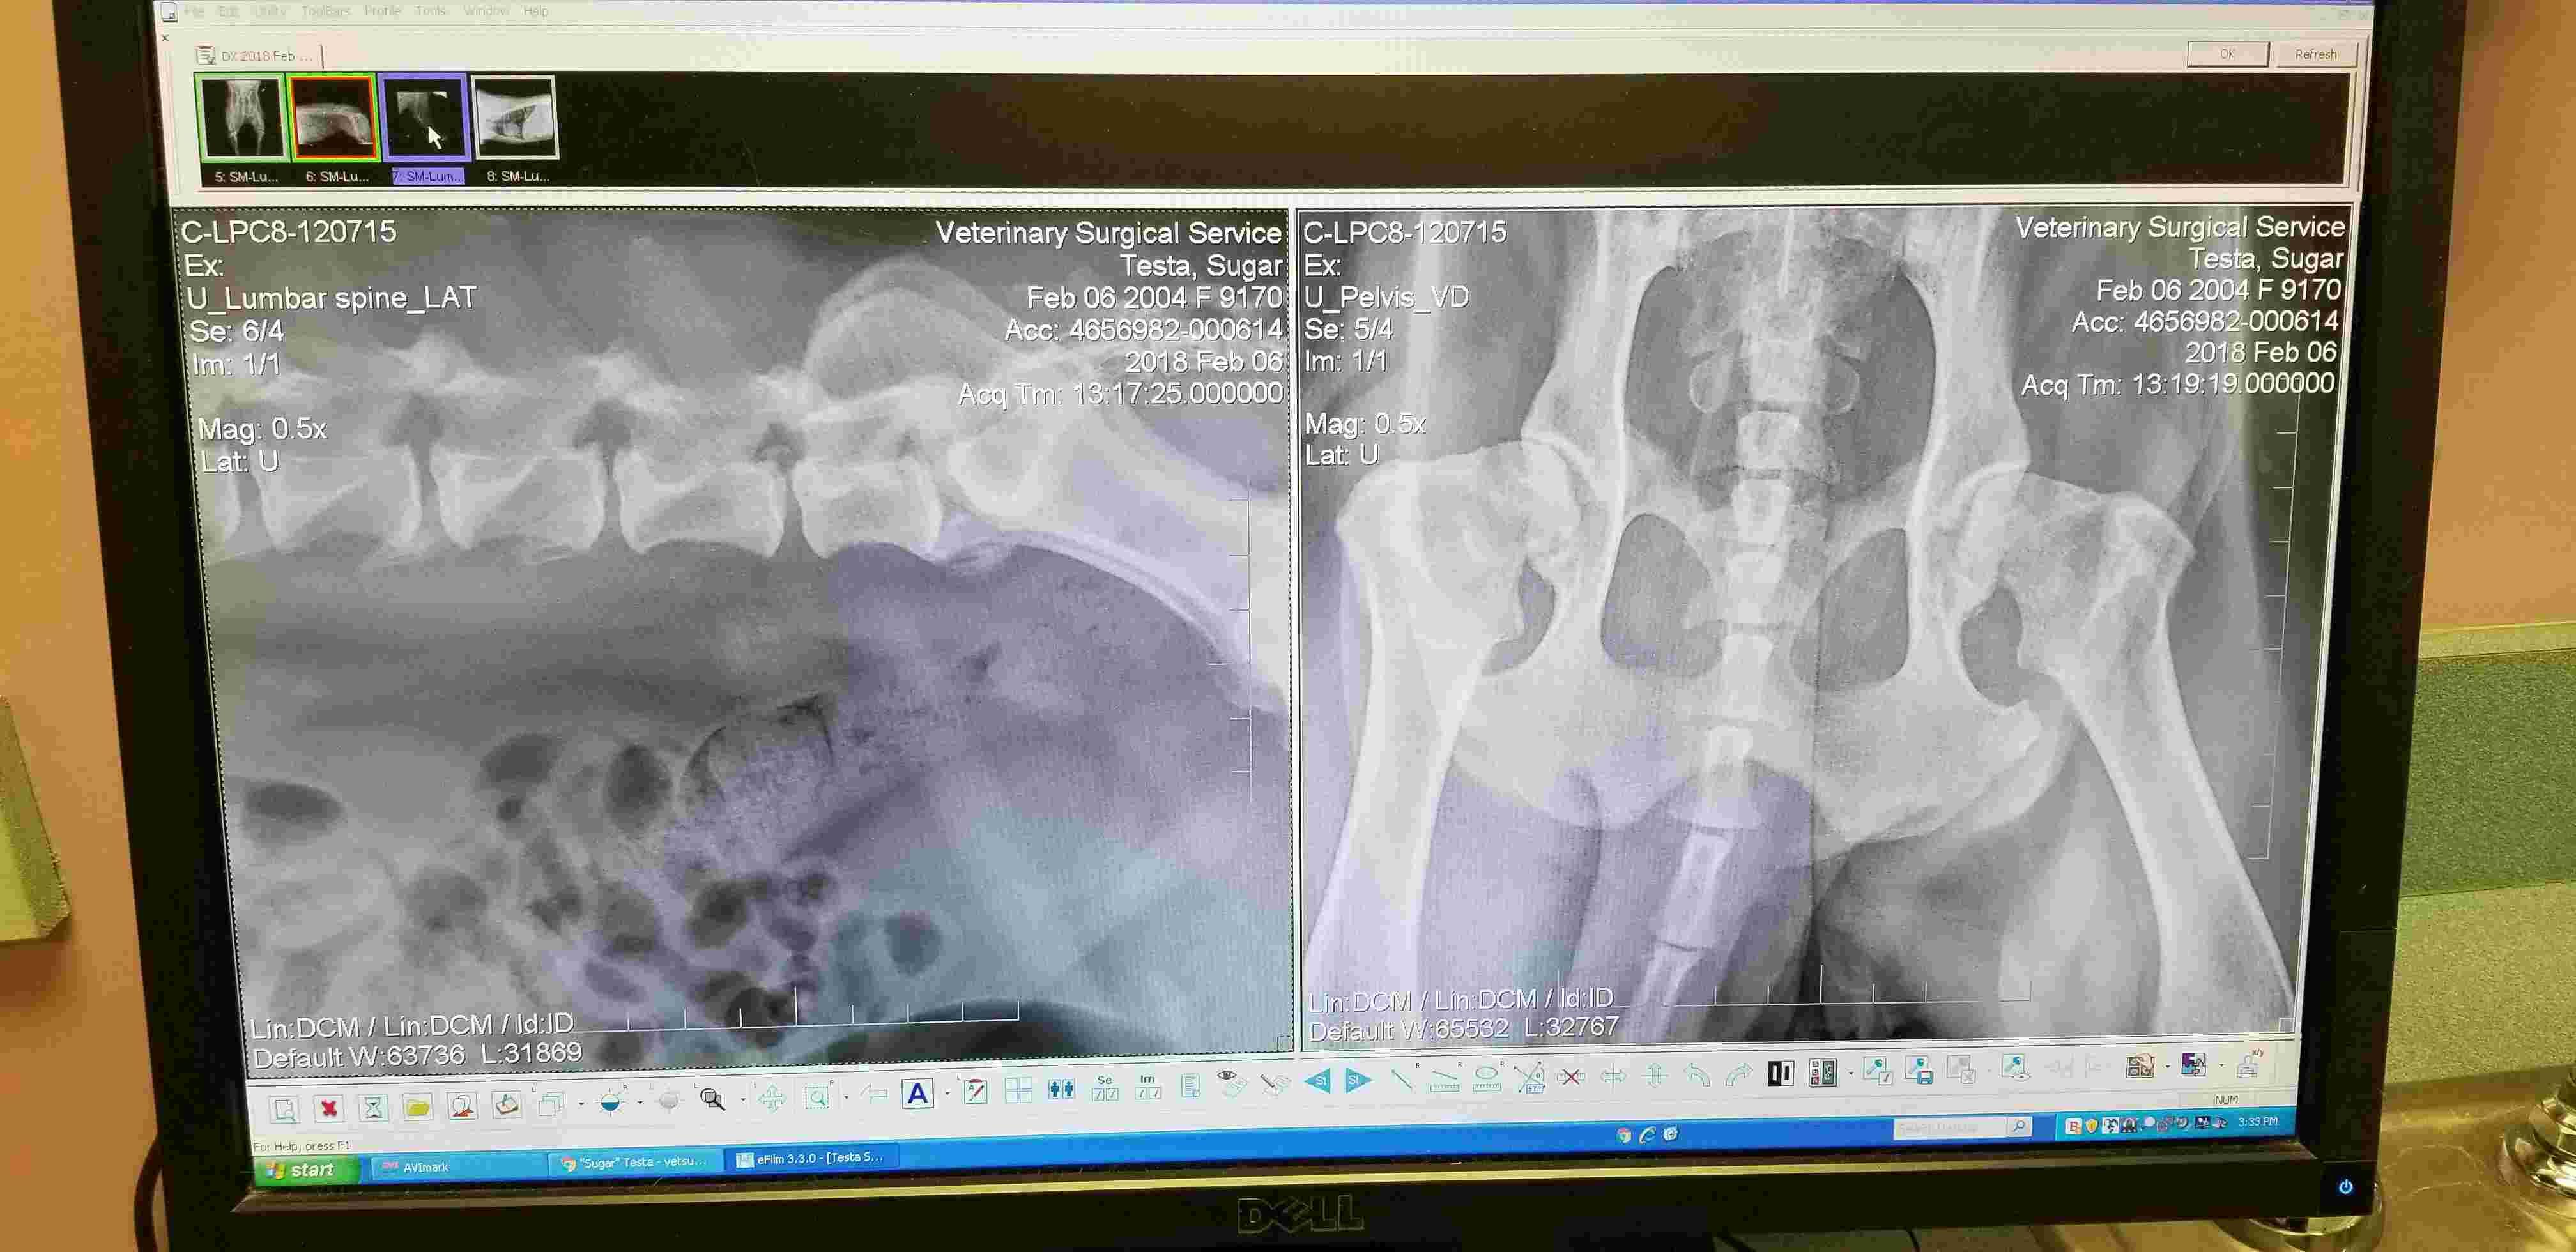

Pet's info: Dog | American Pit Bull Terrier | Female | spayed | 13 years and 8 months old | 45 lbs

Hello. Can you please review my Pitbull's x-rays and see if she has hip dysplasia and/or arthritis? Thanks Joe

Thank you for submitting your question regarding Sugar. She appears to have significant changes to both of her hips indicating severe arthritis. She also appears to have some mild arthritic changes in her left knee. Hip dysplasia is a congenital disorder where the hip joints do not develop properly leading to arthritis later in life. So this is the potential cause of the changes in her hips. I hope she is able to start pain medication to help with her mobility.